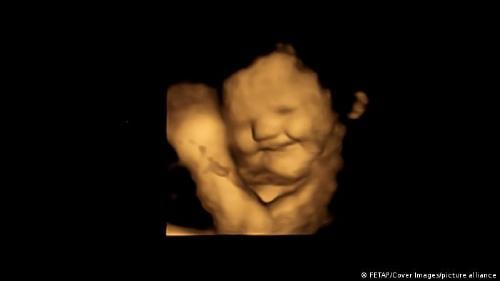

La expresión de la cara de un grupo de bebes aún no nacidos, captada a través de ecografías en 4D, constituye para un grupo de psicólogos la primera evidencia directa de que el feto reacciona a los sabores de los alimentos ingeridos por la madre.

Los fetos expuestos a la zanahoria mostraron más respuestas de "cara de risa", mientras que los expuestos a la col rizada mostraron más respuestas de "cara de llanto", explicó la citada universidad en un comunicado.

El equipo, encabezado por Beyza Ustun de la Universidad de Durham, destacó que fue "realmente sorprendente ver la reacción de los bebés no nacidos a los sabores de la col rizada o la zanahoria durante las exploraciones y compartir esos momentos con sus padres".